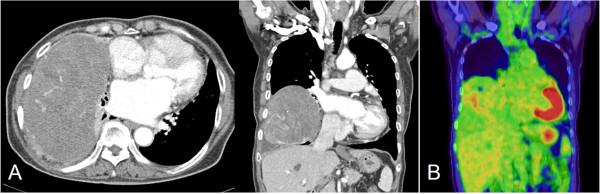

Although a solitary fibrous tumor of the pleura (SFTP) is a rare disease, and usually has a benign course, it has a malignant potential. We report a case of malignant SFTP treated surgically. A 75-year-old female was admitted with a chief complaint of hemoptysis of two weeks duration. Computed tomography of the chest imaged a large mass in the right hemithorax, which compressed adjacent organs; however, there was no evidence of invasion. We reviewed the patient's medical records and found that the mass had been presented for 17 years. Complete resection was achieved through a right thoracotomy and histopathologic examination confirmed a malignant SFTP.

尽管胸膜孤立性纤维瘤(SFTP)是一种罕见疾病,且通常病程呈良性,但它具有恶变潜能。我们报告一例经手术治疗的恶性SFTP病例。一名75岁女性因持续两周的咯血为主诉入院。胸部计算机断层扫描显示右半胸有一个大肿块,该肿块压迫相邻器官;然而,没有侵袭的证据。我们查阅了患者的病历,发现该肿块已存在17年。通过右胸切开术实现了完整切除,组织病理学检查证实为恶性SFTP。